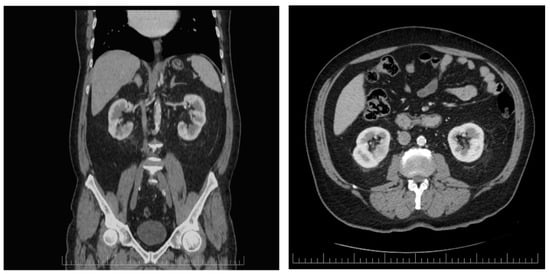

2. Case Presentation

2.1. Diagnostic Assessment